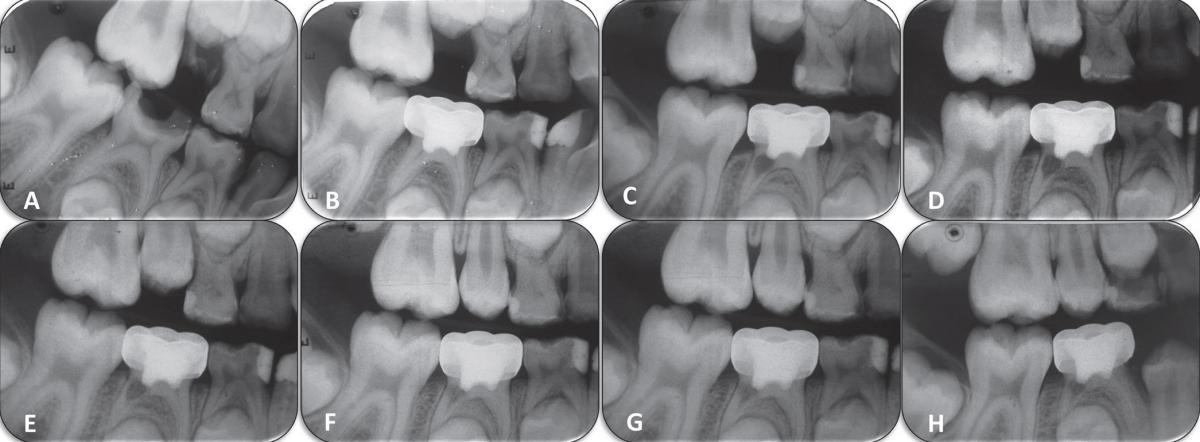

Рентгеновские снимки кариеса корня зуба

Раздел: Визуальные уроки